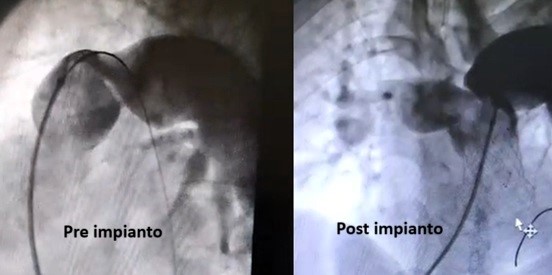

L’équipe dell’Heart Team, formata da specialisti in cardiologia pediatrica e dell’adulto, cardiochirurgia, radiologia e medicina interna, ha escluso l’intervento a cuore aperto per l’alto rischio, optando per una procedura trans-catetered’avanguardia: l’impianto per via endoscopica di una protesi polmonare “auto-ancorante”, senza necessità di circolazione extracorporea.

L’intervento è stato eseguito dal dott. Paolo Guccione, responsabile della Cardiologia Pediatrica, e dal dott. Giuseppe Cinnirella, primario dell’Emodinamica, con il supporto del dott. Gianfranco Butera dell’Ospedale Bambino Gesù. La valvola ha funzionato perfettamente sin da subito, con un miglioramento clinico immediato: già il giorno dopo il paziente ha riportato una netta ripresa respiratoria e ha potuto essere dimesso nella giornata successiva.